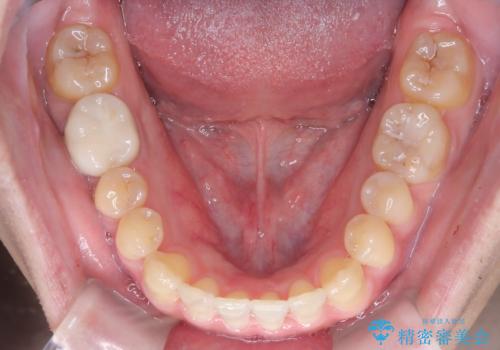

- 前歯の咬み合わせが気になるとのことで来院されました。

前歯が噛んでいない状態(開咬)のため、インビザライン矯正で改善することとしました。

前歯が嚙んでない場合(開咬)、顎間ゴムというゴムを使用してもらうことがあります。顎間ゴムは、前歯を噛み合わせるための力を与える補助的な役割があります。